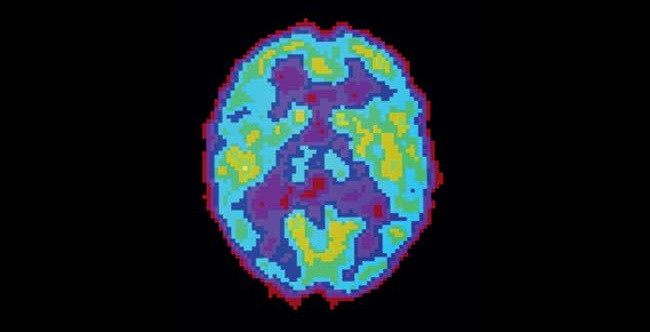

Активность мозга сильно различается не только во время бодрствования и сна — есть множество промежуточных состояний, которые можно различить во время позитронно-эмиссионной томографии.